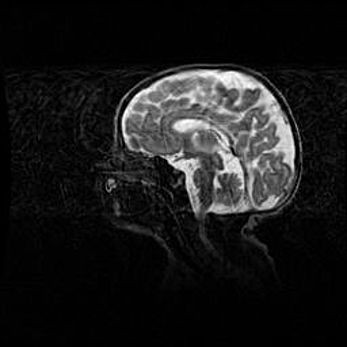

Неполная лизэнцефалия (пахигирия). Открытая гидроцефалия.

Возраст: 17 дней

Вес: 3110 г

Пол: мужской

Окружность головы: 33,5 см

Срок гестации: 35-36 недель

Лизэнцефалия—недоразвитие корковой пластинки и мозговых извилин в результате нарушения миграции нейронов коры. Поверхность мозговых полушарий гладкая. Микроскопически выявляется отсутствие нормальных слоев коры и скопление групп нейронов в подкорковом белом веществе.

Пахигирия—уменьшение числа вторичных извилин. В пораженном полушарии нервные клетки образуют толстый недифференцированный слой с неправильно расположенными нервными волокнами и группами гетеротопных клеток. Нервные клетки незрелые. Белое вещество истончено. При этом нередко аномально развит корково-спинномозговой путь.